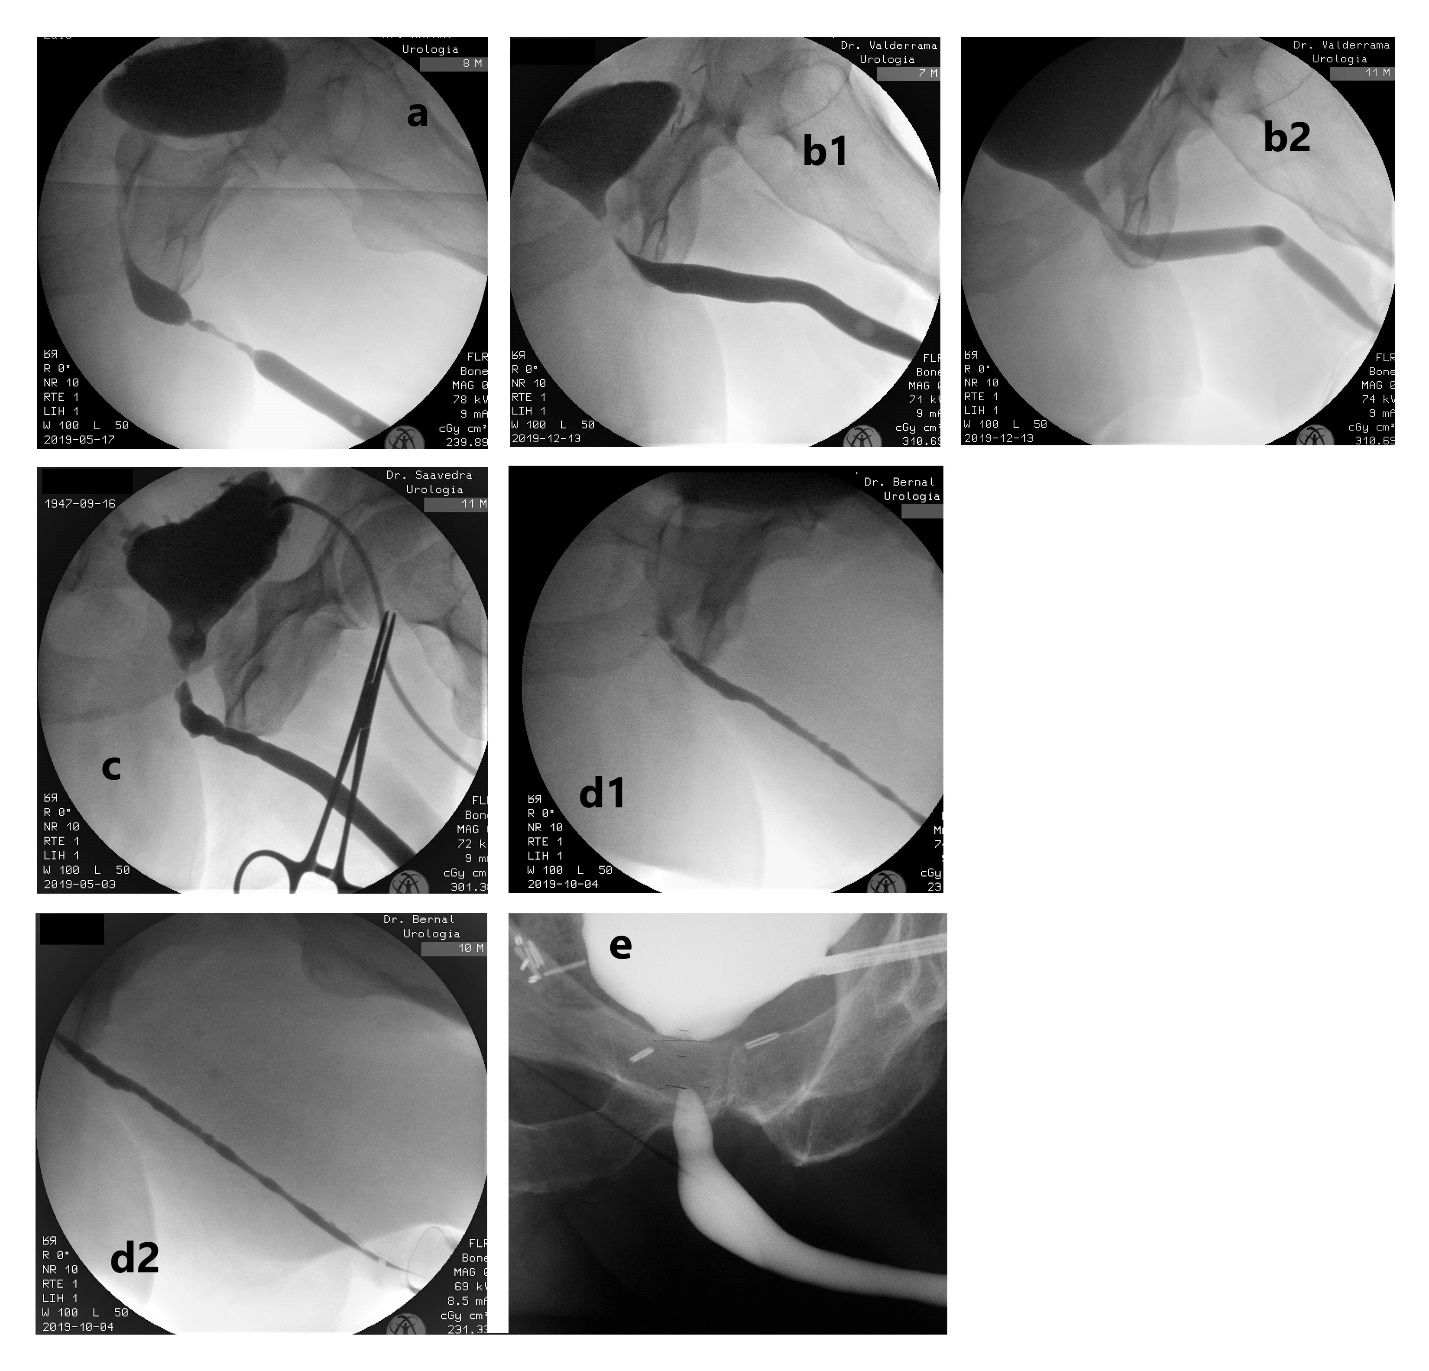

- Uretroplastía. En general, el gold standard en términos de éxito, es la EPA, sin embargo, hay variadas situaciones en que los efectos colaterales la hacen poco aconsejable. Dentro de las técnicas de aumento, la evidencia favorece a los injertos de mucosa oral por sobre los colgajos de prepucio, por el mayor riesgo de complicaciones de éstos últimos, a pesar de tener similares tasas de eficacia. Para decidir la mejor técnica se consideran los siguientes factores: ubicación, longitud, grado de obliteración, etiología, continencia y cirugías previas. (Fig. 7).

| Figura 7. Diferentes imágenes de uretrocistografía. a) Estrechez uretra bulbar media-distal. b1) Estrechez unión bulbomembranosa post-prostatectomía radical + radioterapia (fase retrógrada que no es capaz de definir ubicación real por sí sola). b2) Mismo caso anterior, donde se observa apertura adecuada de la anastomosis uretrovesical y de la uretra membranosa, definiendo la estrechez en la unión bulbomembranosa (fase miccional). c) Estudio anterógrado (por cistostomía) y retrógrado en simultáneo, evidenciando estrechez crítica de unión bulbomembranosa post adenomectomía transvesical; vejiga de lucha y cuello vesical abierto espontáneamente. d1 y d2) Panestrechez de uretra anterior, con segmento crítico en uretra bulbar proximal. e) Estudio con cistoscopía anterógrada flexible y UCG retrógrada en simultáneo, de una estenosis obliterada de la anastomosis uretrovesical post-prostatectomía radical. |